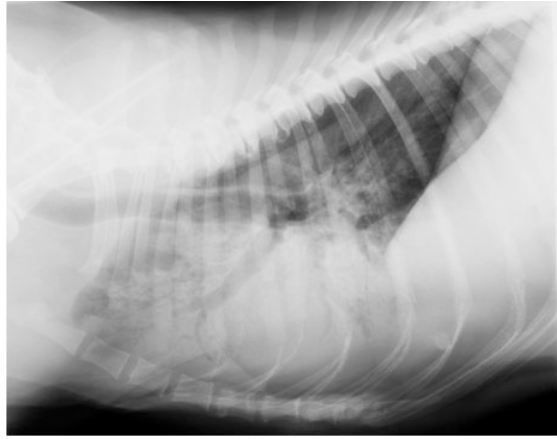

• You are presented with a 9 yr old, female German shepherd dog which stopped eating 5 days previously, has vomited several times and has been dyspnoeic for 3 days prior to radiography. You obtain a plain left lateral thoracic radiograph. What is the predominant lung pattern you can see in the cranial fields?

alveolar